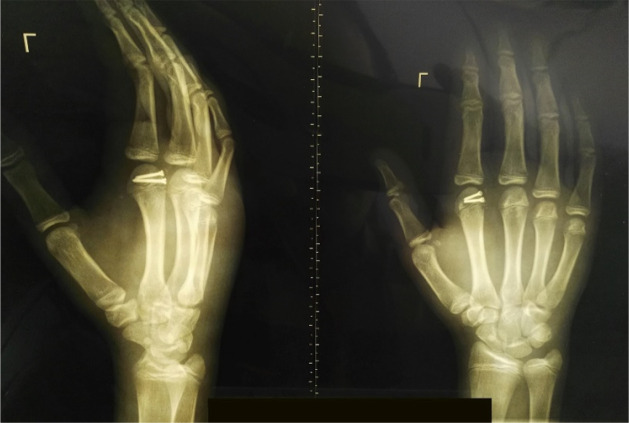

A 14-year-old boy presented to the orthopedic emergency department due to left-hand trauma following a fall on the outstretched hand. On physical examination, the left index MCP joint was swollen, deformed, and tender to palpation. The MCP joint’s active range of motion was restricted to 0-20º (versus the contralateral MCP joint’s active range of motion of 10º extension to 80º flexion). The left-hand x-ray revealed 2nd MCP joint dorsal dislocation and epiphyseal metacarpal head fracture with dorsal-ulnar displacement of the osteochondral segment (figure 1).

Figure 1.

Left hand anteroposterior (left) and lateral (right) radiographs preoperatively demonstrate index metacarpophalangeal joint space widening, index metacarpal epiphyseal head fracture, and dorsal-ulnar displacement of the osteochondral fragment